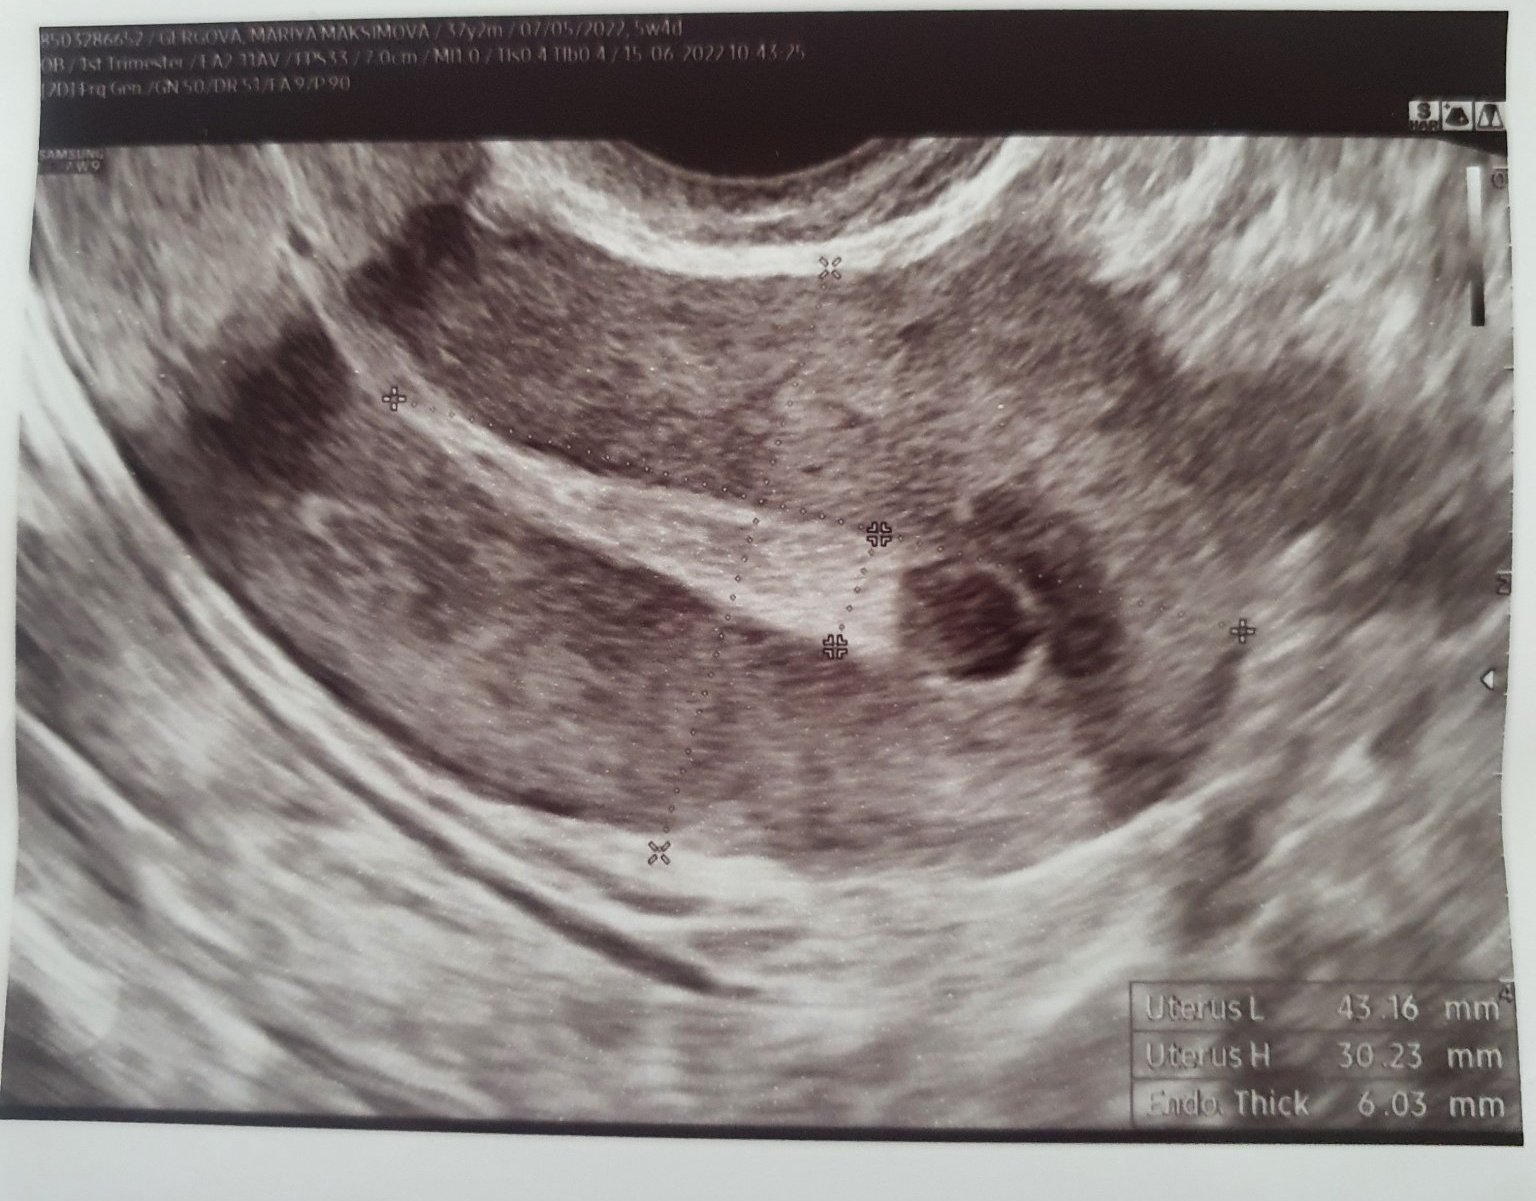

Ето снимките от двата прегледа:

Скрит текст:

Доклад - няма нищо в матката, лигавицата е като след цикъл, НО до десният чйчник визуализира нещо с "инензивна васкуларизация" - пуснахме контролно чхг, за да в сигурна, че не е извънматочна. Макар да каза, че обикновенно дори и да е зивънматочна се визуализира жълто тяло и лигавицата си остава набъбанала.

Их Шантал, как предния път видя сак а сега не?? Явно нещо не е видяла както трябва.

Виждаше се, и аз го видях, но каза, че е с неправилна форма и според нея не е закрепен.

Шантал, аз бих отишла при друг лекар. Няма как да е изчезнал този сак, щом е видян първия път. Особено пък без кървене.